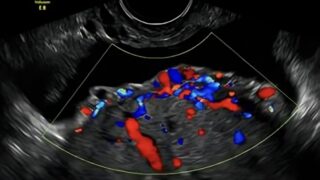

G3P2